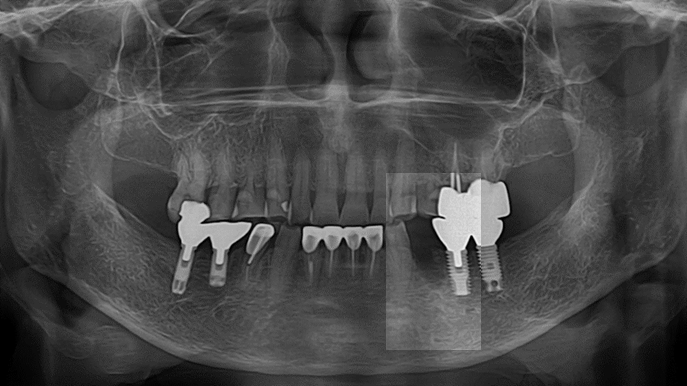

Clinical case: : Immediate loading of lower molars using R2Gate prefabricated 3D-printed provisional restoration

- Courtesy of Dr. Sam Omar, Egypt -

Dr.Sam Omar, immediate loading, digital guided surgery, digital ONE-DAY implant, maxillary anterior, #21, guided surgery, immediate loading, AnyRidge, R2GATE, Mega ISQ, MEG Torq, R2GATE Full Surgical Kit

implant system, R2GATE Guide, R2GATE surgical kit (AnyRidge), Mega ISQ